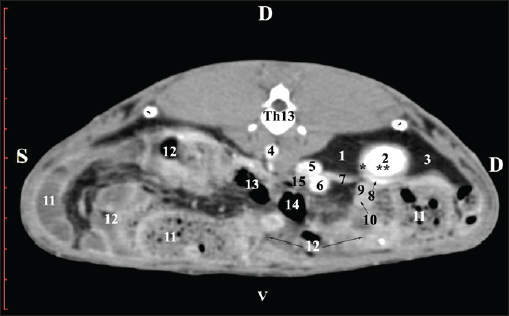

Pre-contrast CT at the Th13 level revealed the right kidney’s extremitas cranialis as a normoattenuated homogeneous soft tissue against the hypoattenuated margins of the lobus hepatis dexter and lobus caudatus (proc. caudatus). Ventrally, the right kidney was in contact with the duodenal par descendens, ileum, and cecum (Fig. 1).

Fig. 1. Pre-contrast computed tomography (CT) anatomical scan of the regio abdominis cranialis at the Th13 level. (1) Lobus hepatis dexter; (2) ren dexter; (3) lobus caudatus (proc. caudatus) with visceral adipose tissue; (4) pars descendens of the duodenum; (5) ileum; (6) gl. adrenalis dextra; (7) colon ascendens; (8) cecum; (9) colon transversum; (10) colon descendens; (*) 13th rib.

At the next scan level (L1), the normoattenuated image of the right kidney was more detailed and in contact with the lobus hepatis dexter, lobus caudatus, duodenal pars descendens, and ileum. The cortex renis and medulla renis were not clearly differentiated. Pelvis renalis appeared as a linear hypoattenuated finding against the relatively normoattenuated kidney cortex and medulla. The proximal part of the ureter was seen medial to the right kidney (Figs. 2 and 3).

Fig. 2. Pre-contrast computed tomography (CT) anatomical scan of the regio abdominis cranialis at the L1 level. (1) Ren dexter; (2) lobus hepatis dexter; (3) lobus caudatus (proc. caudatus) with visceral adipose tissue; (4) pars descendens of the duodenum; (5) ileum; (6) cecum; (7) colon ascendens; (8) colon transversum; (9) colon descendens; (10) jejunum.

Fig. 3. Pre-contrast computed tomography (CT) anatomical scan of regio abdominis cranialis at the L1 level. (1) Medulla renis; (2) cortex renis; (3) pelvis renalis; (4) lobus caudatus (proc. caudatus) with visceral adipose tissue; (5) ureter; (6) pars descendens of the duodenum; (7) jejunum; (8) cecum; (9) colon ascendens; (10) lien; (11) colon descendens; (12) colon transversum.

CT anatomical study at the Th13 level was used to define the right kidney zones. The medulla renalis was found as a hyperattenuated soft tissue with peripheral linear and wavy margins that reached the relatively hypoattenuated renal cortex. The most peripheral structure was the capsula adiposa, characterized by hyperattenuated soft tissue and uniform relief. The hyperattenuated aorta abdominalis, v. cava caudalis, and a. renalis appeared medially to the right kidney (Fig. 14).

Fig. 14. Post-contrast computed tomography (CT) anatomical scan of regio abdominis cranialis at the Th13 level. (1) Lobus hepatis dexter; (2) ren dexter; (3) lobus caudatus (processus caudatus); (4) aorta abdominalis; (5) v. cava caudalis; (6) a. renalis; (7) ureter; (8) capsula adiposa (capsula fibrosa); (9) pars descendens of the duodenum; (10) ileum; (11) cecum; (12) colon ascendens; (13) colon transversum; (14) colon descendens; (15) gl. adrenalis dextra; (black arrowhead) XIII rib; (*) cortex renalis; (**) medulla renalis.